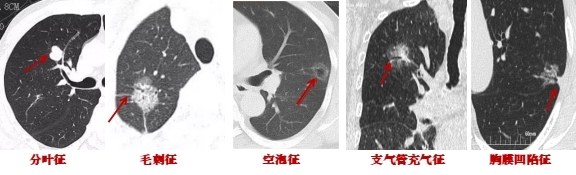

1.結節的形態變化:肺結節持續存在且逐漸增大、密度逐漸增高,惡變可能性大,短期內結節大小急劇變化的多為良性。若結節8mm~15mm,有分葉、毛刺、胸膜牽拉、含氣細支氣管征和小泡征、偏心厚壁空洞這些CT惡性征象,大概率是惡性的。

2.結節的密度:純磨玻璃肺結節惡性概率相對較低,若伴有實性成分且實性成分逐漸增多,惡變可能增大。混合性磨玻璃結節多數為原位癌或早期肺癌。

3.結節與血管的關系:如果肺結節內部有血管匯入,周邊有血管伴行,且血管扭曲、增粗、變細或被中斷,往往提示惡性。